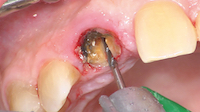

photo n°1 :

Utilisation du périotome (Friatec®) tangentiellement à l’axe de la racine, à l’aide d’un maillet.

photo n°2 :

Segmentation radiculaire à l’aide d’une fraise chirurgicale destinée à faciliter la mobilisation radiculaire.